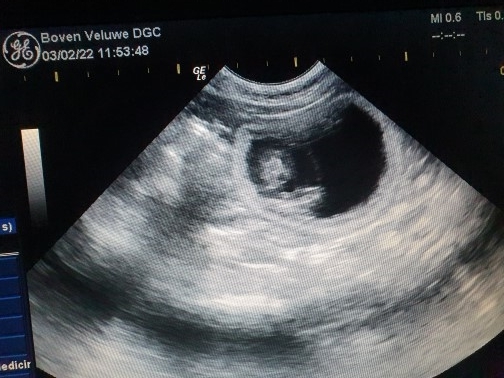

3 februari 2022, de echo om te kijken of Harley drachtig is

de dierenarts telde 6 vruchtjes en 1 lege vruchtblaas.